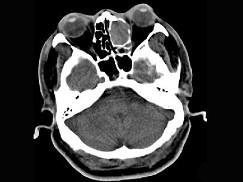

男,34岁,头痛、头晕3个月余,CT检查如图,最可能诊断为 ( )A、筛窦乳头状瘤B、筛窦黏液囊肿C、筛窦炎D、筛窦息肉E、筛窦癌

问题 男,34岁,头痛、头晕3个月余,CT检查如图,最可能诊断为 ( )

选项 A、筛窦乳头状瘤 B、筛窦黏液囊肿 C、筛窦炎 D、筛窦息肉 E、筛窦癌

答案 B